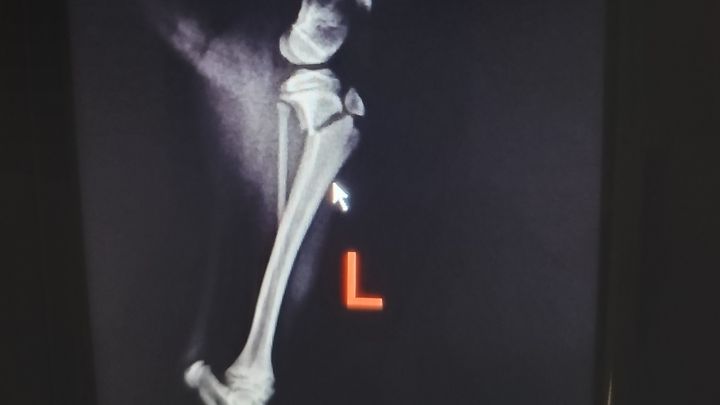

scouting the area three minutes away. Once there they immobilized his leg to avoid further damage and as you can see he has a big fracture and the only explanation might be that he fell from the stairs because he was left out. I am angry, frustrated, in disbelief because I trusted and I shouldn't. I feel like a failed in protecting my furbaby.

The vets office I went to isn't equipped with much and they did what they could and told me to take him to orthopedic surgeon which I did today February 8, 2024. The estimate is included.

I have pain medicine until Saturday I am certain they can prescribe more should I need more time. I am having faith and hope that I receive help during this difficult time to help my furbaby. He is comfortable and isn't in pain but he needs the surgery soon to avoid further damage. I am taking time to be with him around the clock and ensure he doesn't put pressure on his injured leg.